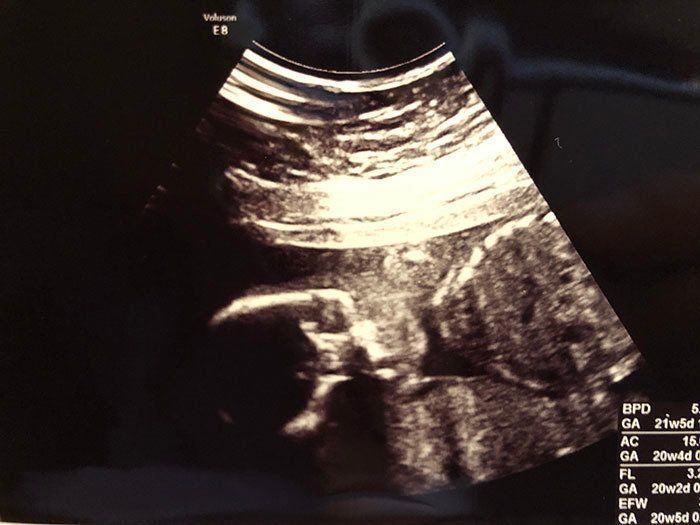

妊娠21週目 つわりからの解放、食欲が少しずつ戻る

妊娠21週目のエコー写真です。すでにつわりが落ち着き、食欲も出てきた頃で、マタニティマークをつけていなくてもバスの席を譲ってもらえるほど、おなかが目立ってきていました。そのせいもあるのか、この時期は腰痛になってしまい、骨盤ベルトを常に締めて過ごしていました。